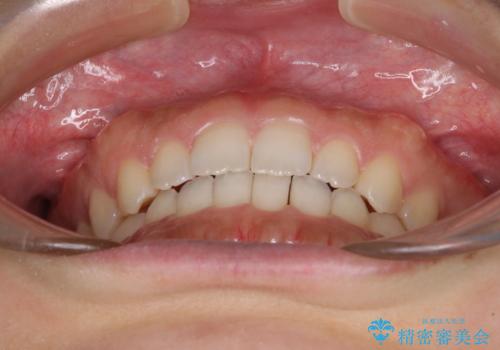

気になる隙間の再矯正 前歯をインビザライン・ライトで改善

- 後戻りによる上下前歯の隙間を気にして来院された患者様です。

歯列不正はそれほど大きくなかったため、インビザライン・ライトを用いて矯正治療を行うこととしました。

無理のないペースで治療を進め、9ヶ月で終えることができました。